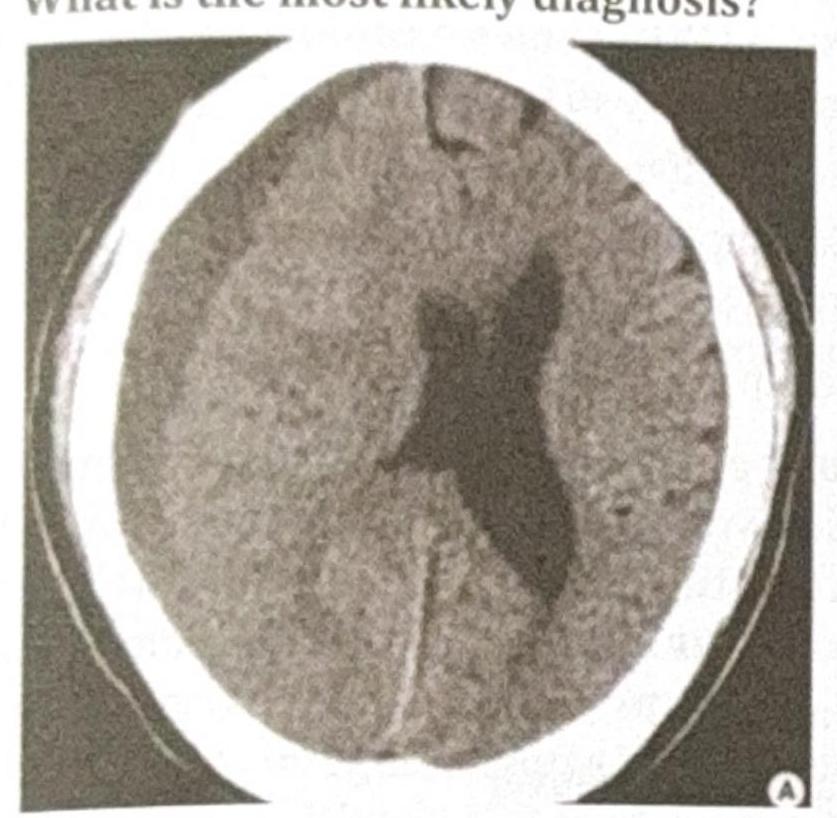

Question 6: An 80-year-old male with a history of frequent falls presents with progressive headache, confusion, and mild hemiparesis over the past few weeks. A CT scan of the head is performed, and the image provided shows a crescent-shaped, hypodense collection over the left cerebral hemisphere with a slight midline shift. What is the most likely diagnosis?

- A. Acute subdural hematoma

- B. Epidural hematoma

- C. Chronic subdural hematoma (Correct Answer)

- D. Intracerebral hemorrhage

Explanation: ***Chronic subdural hematoma*** - The presented CT scan shows a **crescent-shaped, hypodense collection** over the left cerebral hemisphere, which is characteristic of a chronic subdural hematoma. **Hypodensity** indicates older, liquefied blood. - The patient's age (**80-year-old** with **frequent falls**), and the **progressive symptoms** (headache, confusion, mild hemiparesis over weeks) are highly consistent with a chronic rather than acute presentation. *Acute subdural hematoma* - An acute subdural hematoma would typically present as a **hyperdense** (bright) crescent-shaped collection on CT due to fresh blood. - Symptoms would usually be more acute and severe, developing over hours to days, which does not match the "past few weeks" progression. *Epidural hematoma* - An epidural hematoma is typically **lens-shaped (biconvex)**, not crescent-shaped, and usually results from a traumatic arterial bleed. - While it can cause midline shift, its characteristic shape and often acute presentation (often with a lucid interval) differentiate it from the described scenario. *Intracerebral hemorrhage* - An intracerebral hemorrhage occurs within the brain parenchyma, appearing as a **hyperdense mass within the brain tissue** on CT, not as a collection over the cerebral hemisphere. - The symptoms would depend on the location but would not typically involve a crescent-shaped collection outside the brain parenchyma.